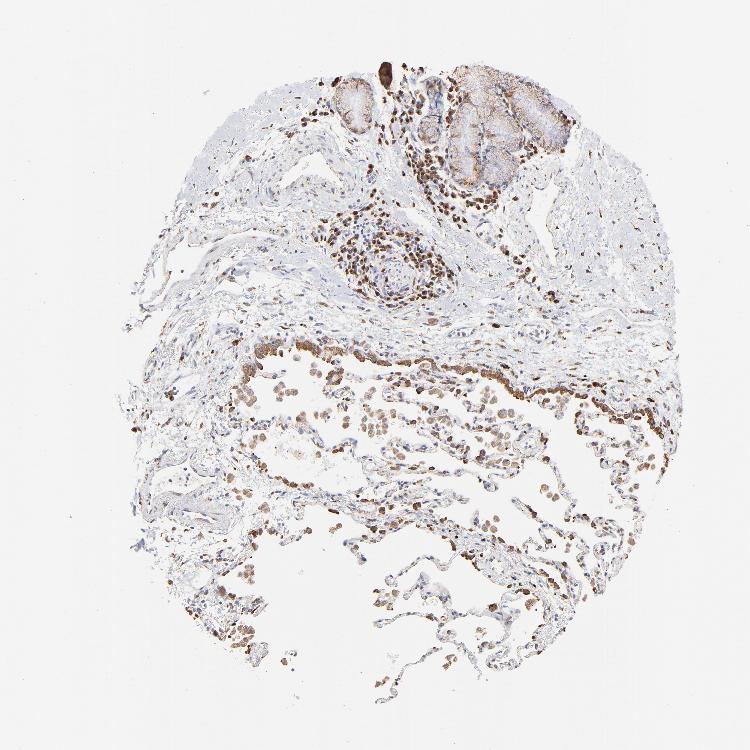

SOFT TISSUE 1 - Antibody stainingi

Antibody staining in the annotated cell types in the current human tissue is reported as not detected, low, medium, or high, based on conventional immunohistochemistry profiling in selected tissues. This score is based on the combination of the staining intensity and fraction of stained cells.

Each image is clickable and will lead to virtual microscopy that enables deeper exploration of all samples and also displays staining intensity scores, fraction scores and subcellular localization as well as patient and tissue information for each sample.

Antibody HPA002320Antibody CAB037163

Chondrocytes -Medium

Fibroblasts MediumMedium

Peripheral nerve MediumNot detected

SOFT TISSUE 2 - Antibody stainingi

Peripheral nerve Not detectedNot detected